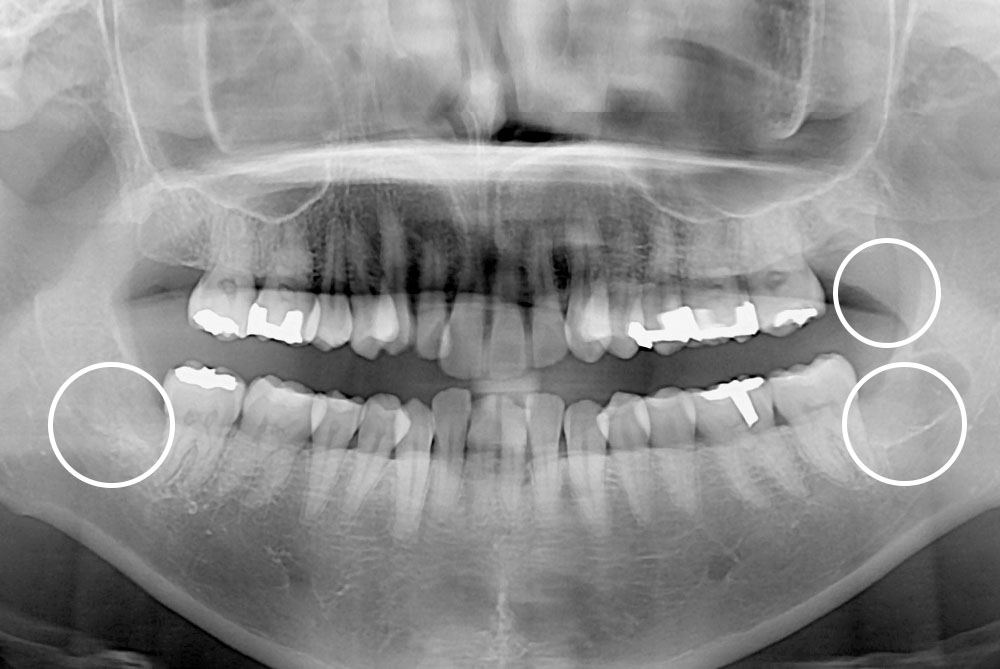

[사랑니] 매복 사랑니 발치

치료후 : 2018-12-05

세종치과는 구강악안면외과학 박사이신 원장님이 발치하는 치과입니다.